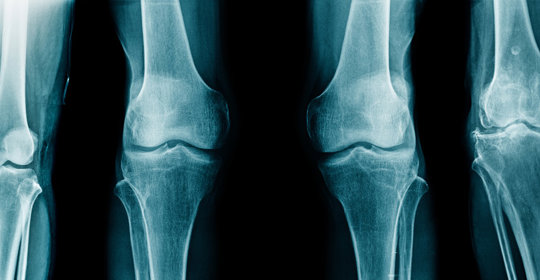

本文介紹了骨軟骨瘤與骨癌的區別。骨軟骨瘤是一種常見的良性骨腫瘤,而骨癌則屬於惡性腫瘤。雖然骨軟骨瘤通常不會引起疼痛,但並不代表病情好轉,仍需定期隨訪和醫學評估。對於這兩種疾病,建議患者及時就醫並接受專業治療。